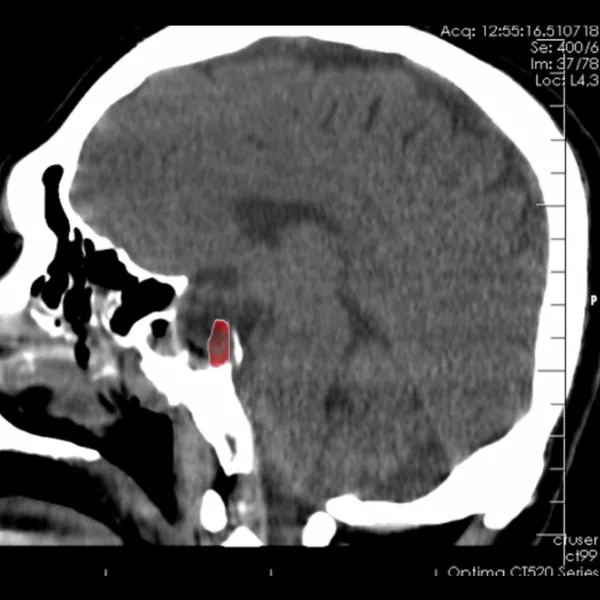

Doktor Ahmet Sinan Tıraş, bu hastalığın basit bir bulantı ve kusma olmadığını ve görme kaybıyla birlikte ciddi bir nörolojik durum olduğunu düşünerek, Nöroloji Doktoru Uzm. Dr. Ceren Kuşakçı’yı bilgilendirdi. Uzm. Dr. Ceren Kuşakçı Tomografi ve MR çekilmesini istedi. Beyin ve Sinir Cerrahisi Doç. Dr. Mehmet Gazi Boyacı ile birlikte MR ve Tomografi sonuçlarını inceleyen hekimler, Hipofiz bezinin altında dev hipofiz adenomu ile karşılaştı. 4 santimetrenin üzerindeki bu kitle; görme sinirlerine baskı yaptığı için görme kaybı oluşan hastaya Göz Hastalıkları ve Sağlığı Doktoru Op. Dr. Mustafa Muhterem Ekim tarafından yapılan tetkikte yüzde 90 görme kaybı olduğu tespit edildi.

Görme sinirlerine baskı giderek arttığı için Beyin ve Sinir Cerrahisi Doç. Dr. Mehmet Gazi Boyacı tarafından acil ameliyat olması gerektiğine karar verildi. Ancak ameliyat için 2 farklı yol olduğunu dile getiren Doç. Dr. Mehmet Gazi Boyacı; kafatasının kesilerek iyileşme süreci uzun olan yöntem yerine, burundan girilerek kitleyi çıkarmanın daha mantıklı ve iyileşme sürecini kısaltan bir ameliyat tekniği olduğunu düşündü.

Kulak-Burun-Boğaz Doktoru Op. Dr. Ersen Koç ile birlikte Transsfenoidal Sinüs Cerrahi(burundan girilerek Sfenoid Sinüs yoluyla yapılan ameliyat) ameliyatı olmasına karar verildi. Ameliyat sonucunda hipofiz bezindeki kitlenin tamamına yakını burnundan çıkarılarak hastanın görme sinirlerindeki baskı ortadan kaldırıldı. Doktorlarımız ve ekibimizin titizlikle yürüttüğü operasyon sonucunda hasta sağlığına kavuştu ve ameliyattan hemen sonra görme oranı yüzde 10’dan yüzde 90’a yükseldi.